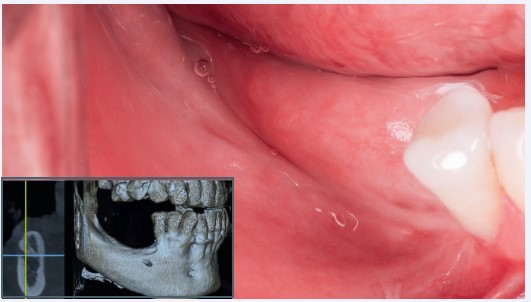

Paciente masculino, 52 anos, compareceu à clínica com queixa de ausência dentária inferior posterior bilateral e desejo de reabilitação com implantes dentários. Ao exame clínico, verificou-se uma mucosa alveolar fina e a ausência de gengiva queratinizada nas regiões edêntulas. A tomografia computadorizada de feixe cônico (TCFC) evidenciou a reabsorção óssea severa, comprometendo a instalação direta dos implantes dentários (Fig. 1).

Figura 1: Aspecto inicial e exame tomográfico inicial